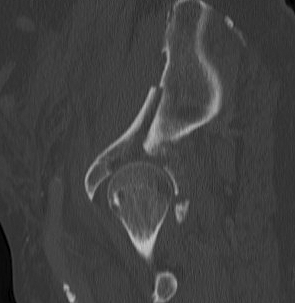

CT

Configuration

1-2 mm sections

CT reconstruction

- remove head to view acetabulum

- beware volume averaging

- used to guide surgery

Diagnose

Loose bodies

Femoral head fractures

Subtle subluxation

Articular steps

Roof arc measurement